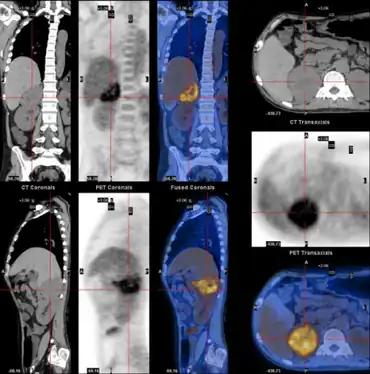

WDHA caused by pheochromocytoma-,PET-CT scan demonstrating well defined adrenal mass